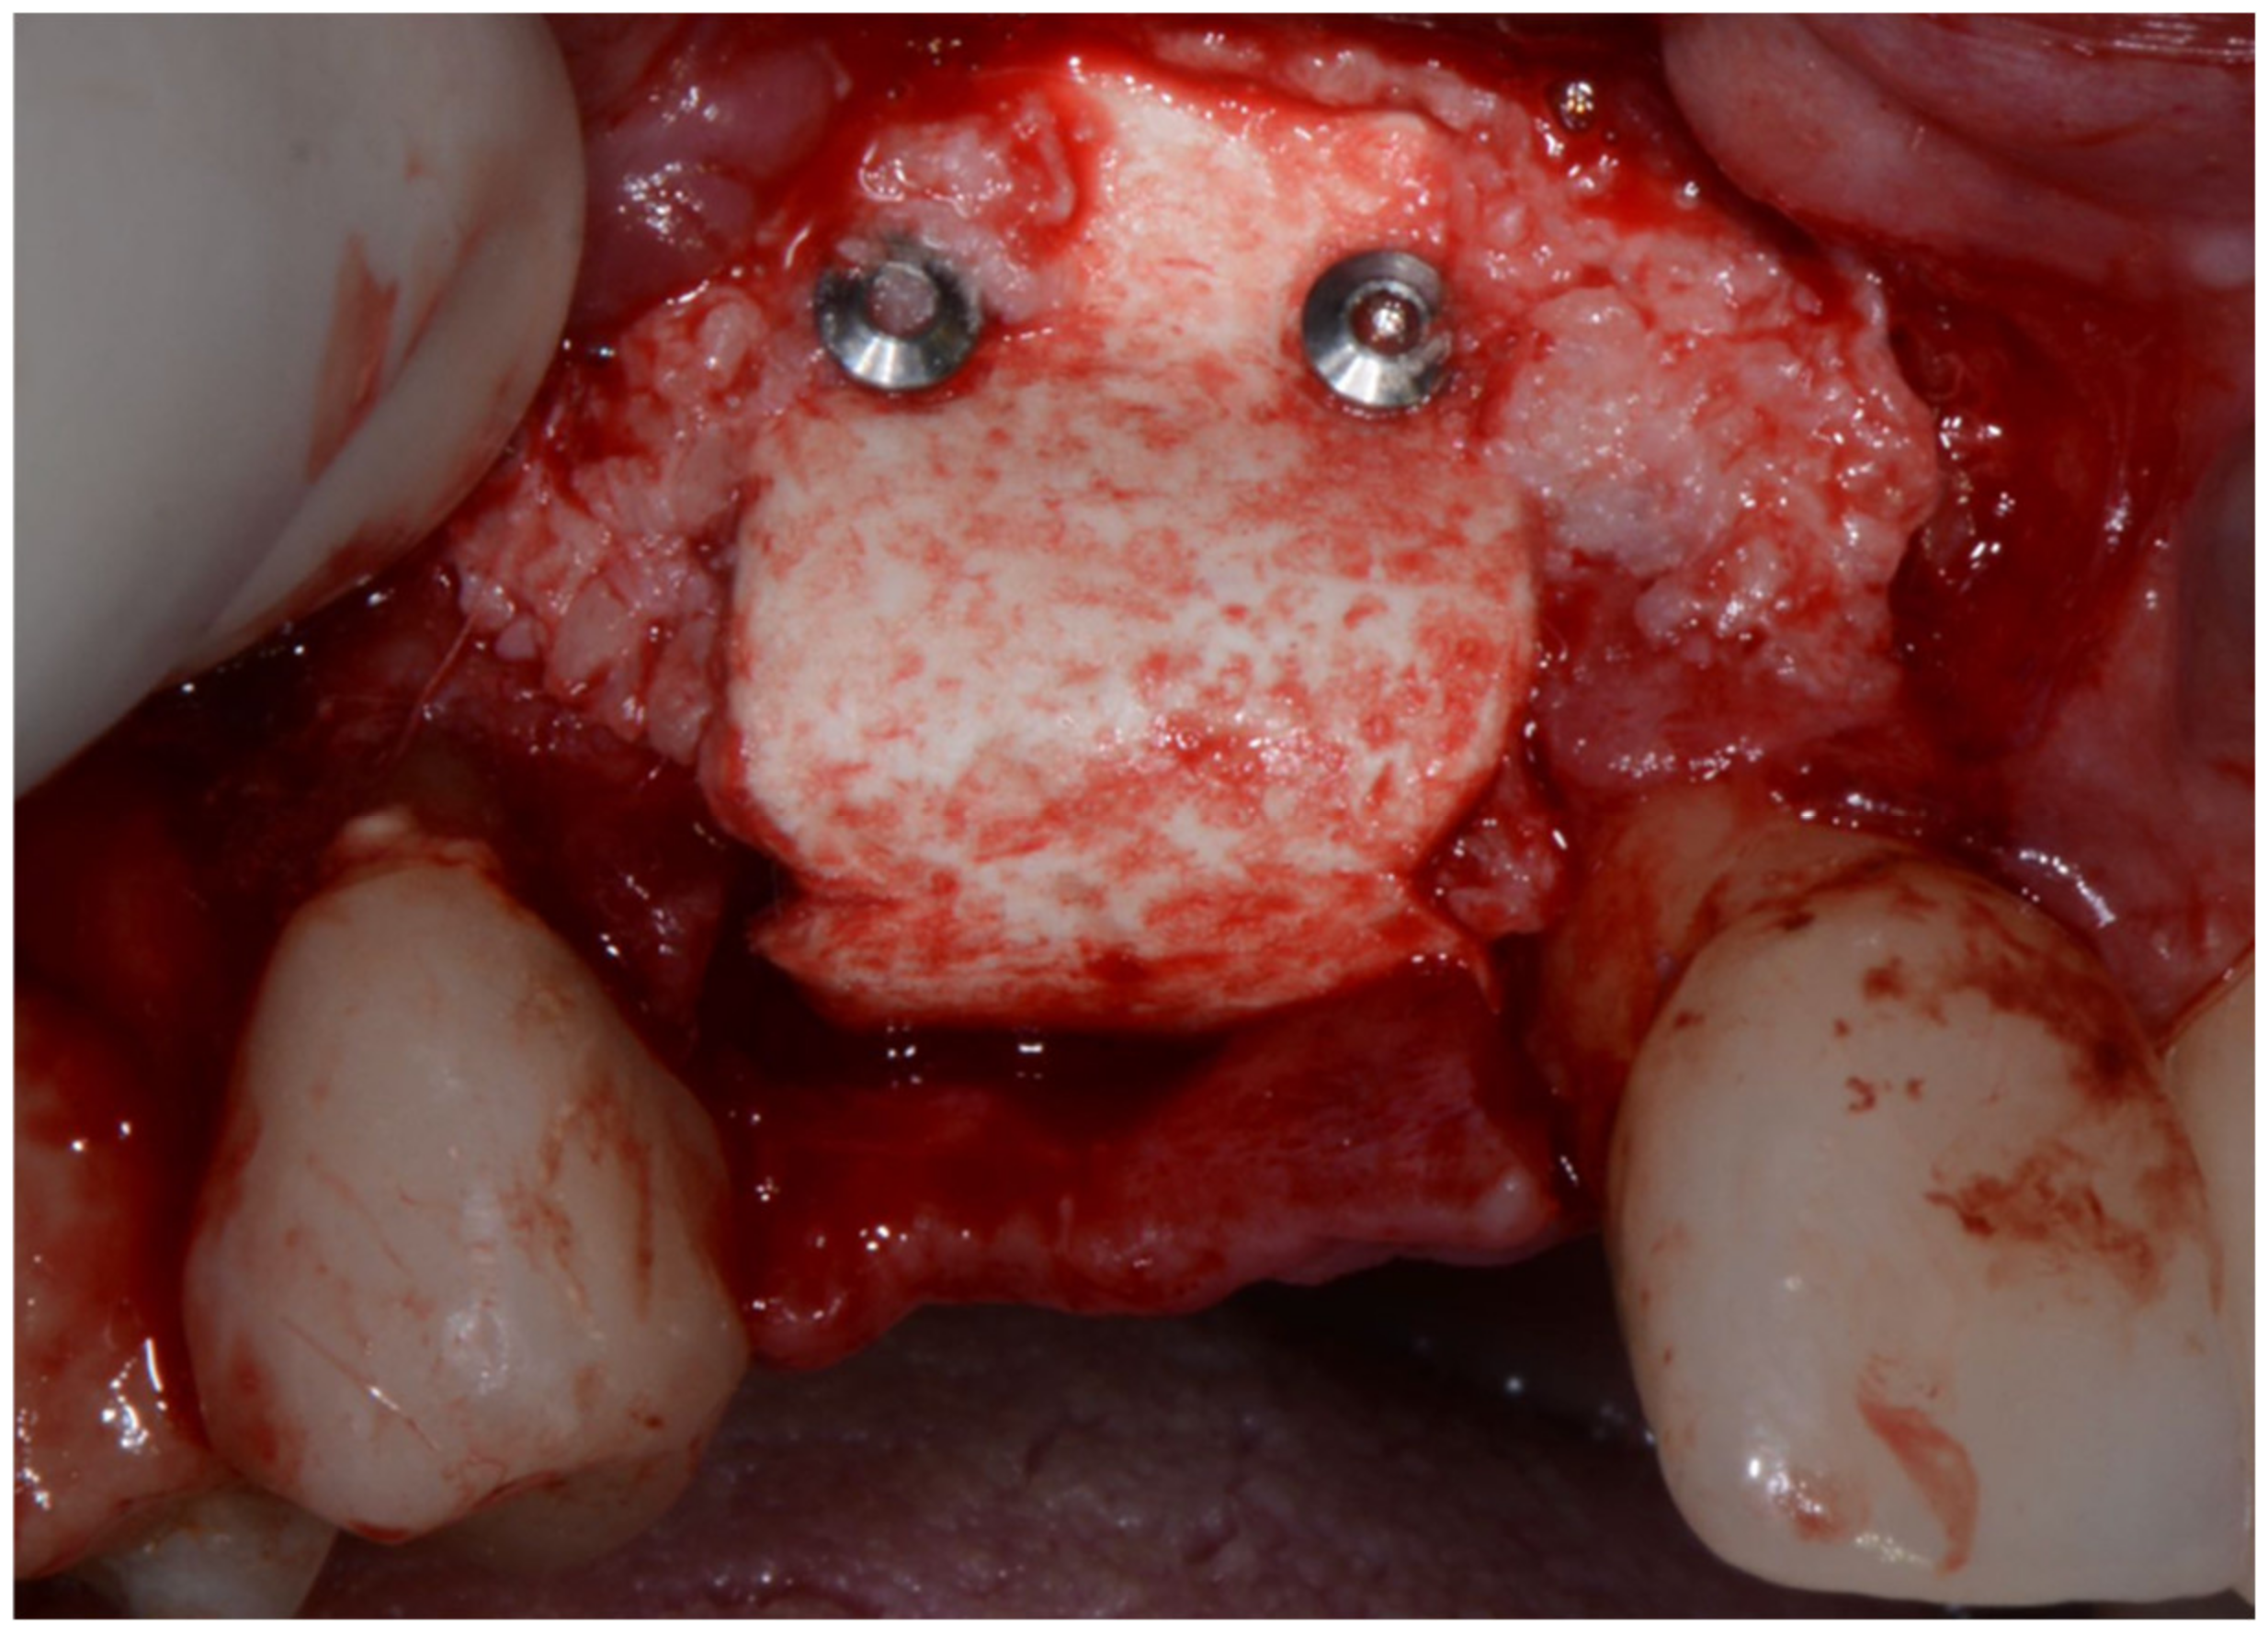

The bone lamina was shaped as a saddle, fixed to the buccal bone with two pins, and then, after the area was grafted with a mix of autogenous bone and collagenated xenograft (50–50%), reflected and stabilized under the palatal flap (Figure 7). Flaps were secured with 4.0 resorbable sutures and healing was uneventful.

Figure 7.

Bone lamina in place, arrows indicate the thickness of the lamina (1 mm) inducing both GBR and GTR effect.